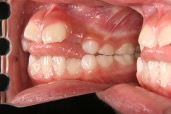

図10 症例1正面

症例1。犬歯の根元が露出しているため上顎左右の犬歯を抜歯して治療しました。下の前歯は上の歯と強くぶつかっているため初めはブラケットがつけられません(図12)。

下の歯は抜歯していません。治療前は見えなかった下顎の前歯が見えています(図13,14)。

図14 症例1(治療後横)